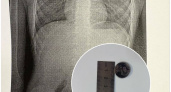

В Новороссийске врачи «выловили сачком» литиевую батарейку из желудка 7-летнего ребенка